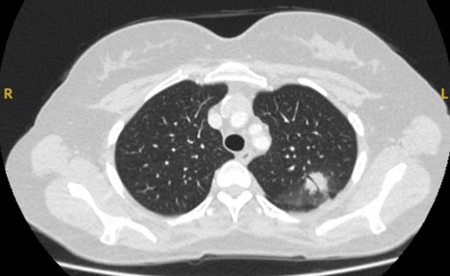

Semi-solid nodules: growth of the solid component suggests that further investigation and/or treatment should be considered.[Figure caption and citation for the preceding image starts]: Computed tomography (CT) sections with examples of semi-solid solitary nodulesFrom the collection of Dr George Tsaknis, MD, PhD, FRCP(London), MRQA, MAcadMEd, PGCert; used with permission [Citation ends].